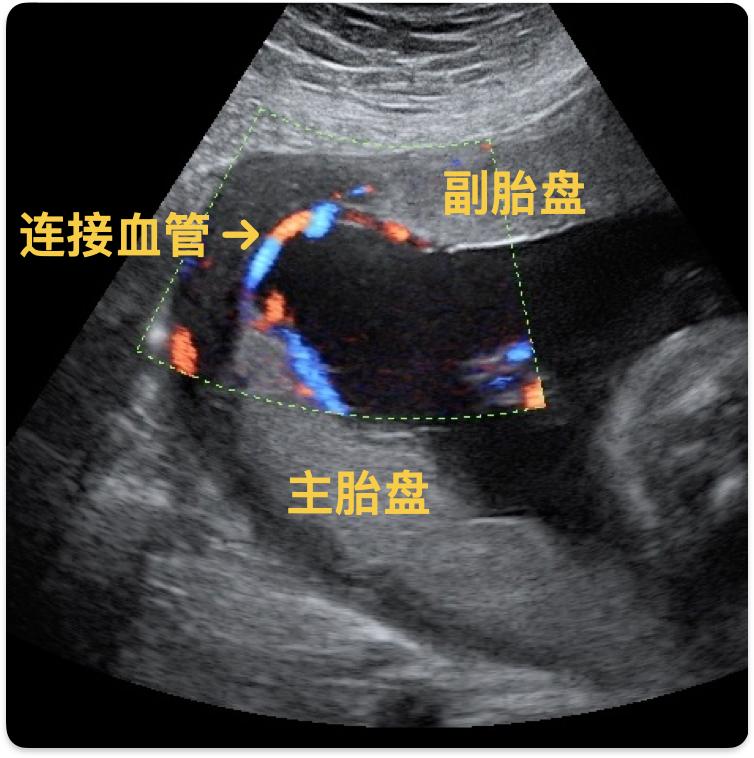

本文作者有两个胎盘的情况,被称为副胎盘,是胎盘的一种形态学问题。这是指主胎盘周边一段距离的胎膜内,有1个或数个胎盘小叶发育,副胎盘与主胎盘之间有胎儿来源的血管相连。副胎盘的结构特点与主胎盘一样,通常不会引起症状,主要是通过孕期超声检查发现。

副胎盘一般不会在孕期对孕妇及胎儿造成影响,但在胎儿娩出时及分娩后,可能会引起一定风险。如果副胎盘存在低置情况,有可能造成阴道流血。根据本文提供信息,作者出血原因有可能就是副胎盘合并胎盘低置。有时,连接副胎盘和主胎盘的血管可能会有前置性,在分娩过程中,有可能造成胎儿宫内窘迫。

超声下的副胎盘 | Case courtesy of Alexandra Stanislavsky, Radiopaedia.org, rID: 13449参考文献